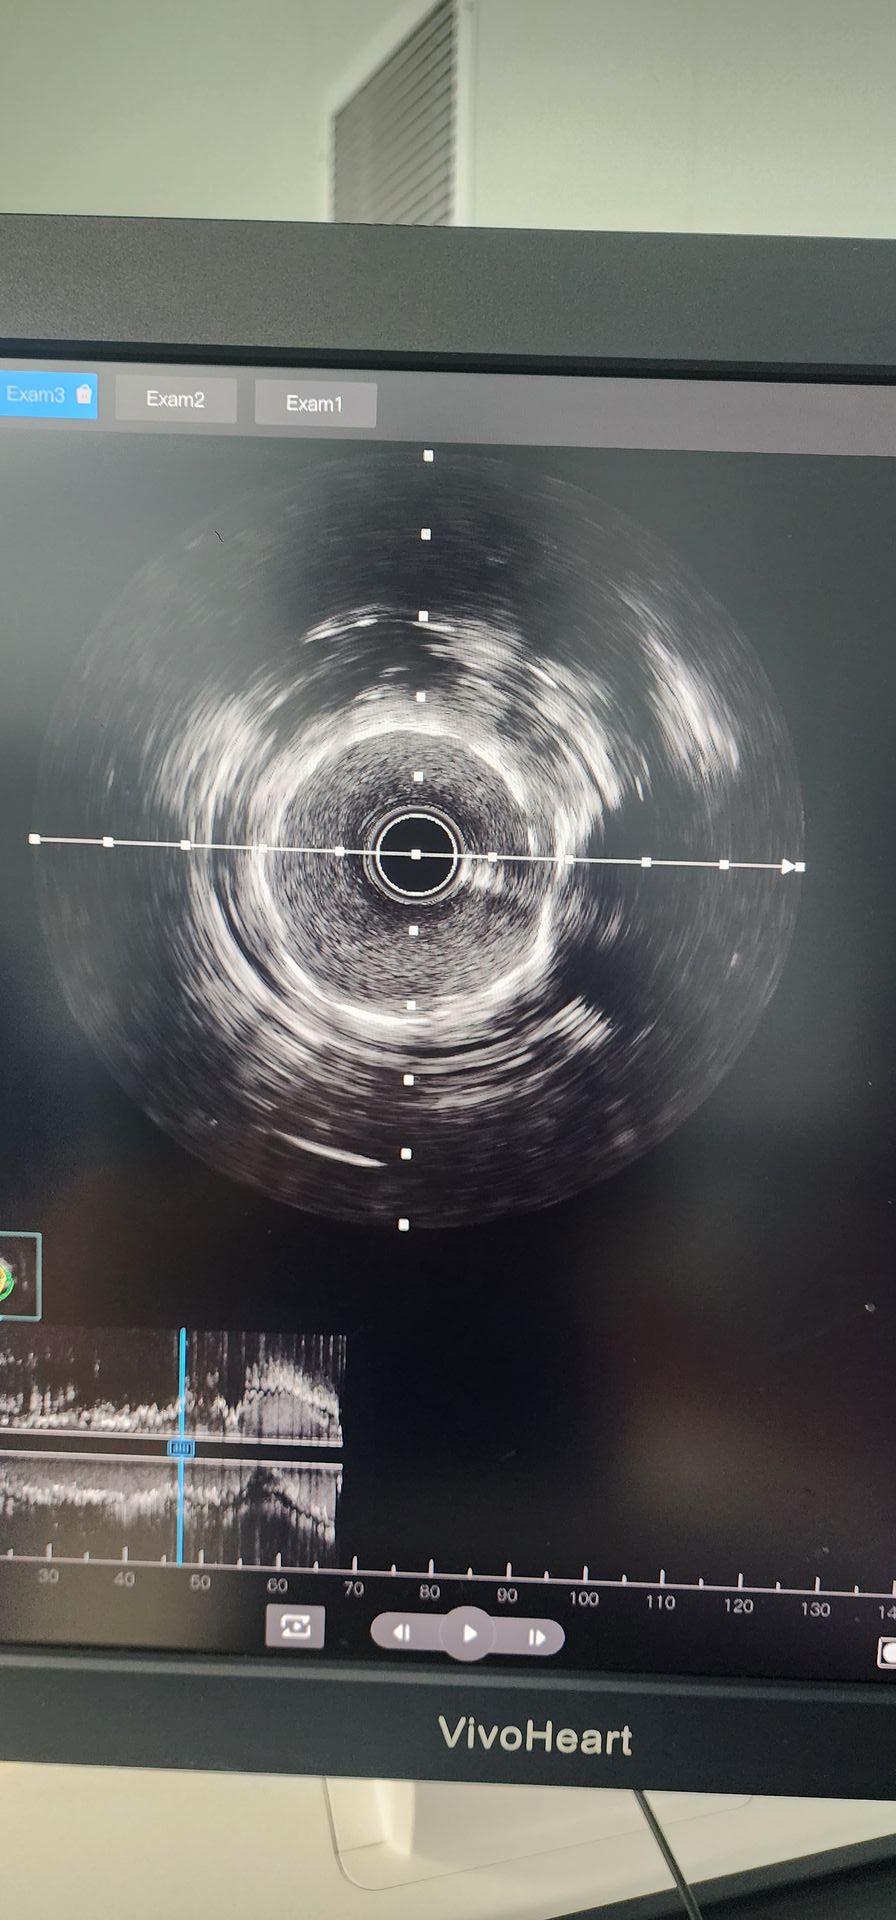

Coronary angiography revealed severe calcification with 95% stenosis in the proximal circumflex artery and 85%–90% calcified stenosis in the mid-right coronary artery.

Proximal Circumflex Artery: Initial pre-dilation with a 2.0×20 balloon showed poor results. A 2.5×12 Lepu Vesscrack Coronary IVL Balloon Dilatation Catheter was then used, delivering four cycles, successfully fracturing the calcified lesion. After significant improvement in stenosis, a 2.5×14 stent was successfully implanted, with satisfactory angiographic results.

Mid-Right Coronary Artery: Initial pre-dilation with a 2.5×20 balloon resulted in limited improvement. A 2.5×12 Lepu Vesscrack Coronary IVL Balloon Dilatation Catheter was then used for two cycles, significantly improving the stenosis in the calcified lesion. A 3.0×19 stent was then successfully implanted, yielding satisfactory angiographic results.